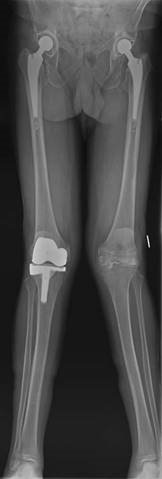

This is a picture of a 67-year-old woman with a painful left knee. The pain has been increasing over the last 3 years. She is otherwise fit and well and has had previous joint replacements as shown.

How would you manage this patient?

I would establish from the history more about her pain, disability, and what treatment she has so far received. On examination I would look at the nature of the deformity, whether it is correctable, the integrity of the medial collateral ligament, patella tracking, and neurological status (common peroneal nerve). I would examine her hip and foot. I would arrange some radiographs including standing AP, lateral. Von Rosenberg views and a skyline patella can be useful with valgus deformities. I may want a long leg fi lm.

T reatment would include maximizing conservative measures. If this failed I would discuss with the patient knee arthroplasty surgery (lateral unicompartmental or total).

How would you consent the patient for a TKR?

I would describe the procedure as well as alternative treatments. I would describe the anticipated outcome in terms of pain relief; functional outcome, and longevity. I would explain the risks and complications of the surgery. General risks and specifi c risks for TKRs as well as specifi c risks for valgus TKRs.

Describe your plan for surgery in this case. z Correct indications met z Patient fully consented z Antibiotic prophylaxis z Choice of implant z Choice of approach z Principles of bony cuts, especially rotation of femoral componentโ h ow I will assess this (hypoplastic or wear on posterior lateral femoral condyle makes posterior referencing inaccurate)

z What I will do with the patella z Soft tissue balancing (sequence of releases) z Implantation of prosthesis and cementing technique z Drain?

z Post-operative management and DVT prophylaxis z Follow-up